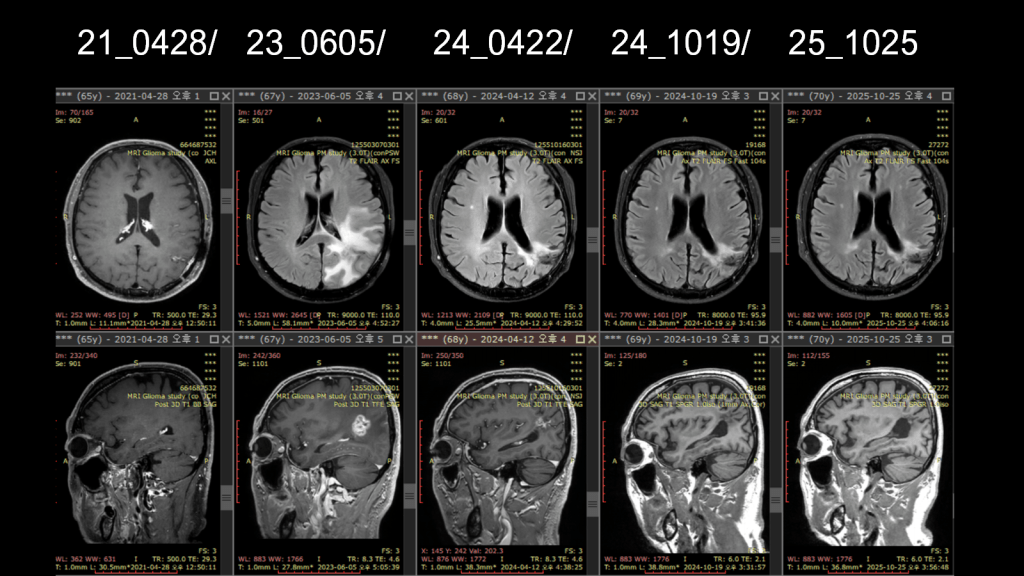

2021-04-28: Brain MRI

A small enhancing nodule measuring approximately 0.9 cm was identified in the left parietal lobe.

The interval change was described as equivocal, meaning that definite progression could not be clearly determined.

2023-06-05: Brain MRI

The enhancing nodule showed further increase in size.

Findings were interpreted as more suggestive of progressive disease (PD) rather than radiation-related change.

Brain MRI Follow-up Summary (2024–2025)

April 12, 2024 – Brain MRI

Decrease in the extent of the irregular enhancing lesion in the left parietal lobe.

October 19, 2024 – Brain MRI

Further decrease in the extent of the irregular enhancing lesion.

April 26, 2025 – Brain MRI

Continued decrease in lesion extent. Findings are more suggestive of treatment-related changes rather than tumor recurrence.

October 25, 2025 – Brain MRI (Latest)

No newly visible measurable enhancement. No change (NC) in the extent of the pre-existing irregular enhancing lesion, indicating a stable condition.